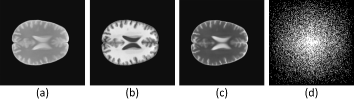

III Forest Sparsity

In practical applications, it happens usually that multi-channel images, such as color images, multispectral images and MR images, have the joint sparsity and tree sparsity simultaneously. It is because: (a) the wavelet coefficients of each channel naturally yield a quadtree; (b) all channels represent the same physical objects (e.g. nature scenes or human organs), and the wavelet coefficients of each channel tend to be large/small simultaneously due to same boundaries of the objects. Therefore, the support of such data is consist of several connected trees and like a forest. Fig. 1 shows the forest structure in multi-contrast MR images. We could find that the non-zero coefficients are not random distributed but forms a connected forest. Unfortunately, existing tree-based algorithms can only recover multi-channel data channel-by-channel separately, and it is unknown how to model the tree structure in existing joint sparsity algorithms. In addition, there are no theoretical results in previous works showing how much better the recovery can be improved by fully exploiting the prior information.

Figure 1: Forest structure on multi-contrast MR images. (a) Three multi-contrast MR images. (b) The wavelet coefficients of the images. Each coefficient tends to be consistent with its parent and children, and the coefficients across different trees at the same position. (c) One joint parent-child group across different trees that used in our algorithm.

Motivated by this limitation, we extend previous works to a more special but widely existed case. For multi-channel data, if it is jointly sparse, and more importantly, the common support of different channels yields a subtree structure, we call this kind of data forest-sparse data:

where g𝑔g denotes one of the coefficient groups discussed above (an example is demonstrated in Fig.1(c)), ()gsubscript𝑔(\cdot)_{g} denotes the coefficients in group g𝑔g and 𝒢𝒢\mathcal{G} is the set of all groups.